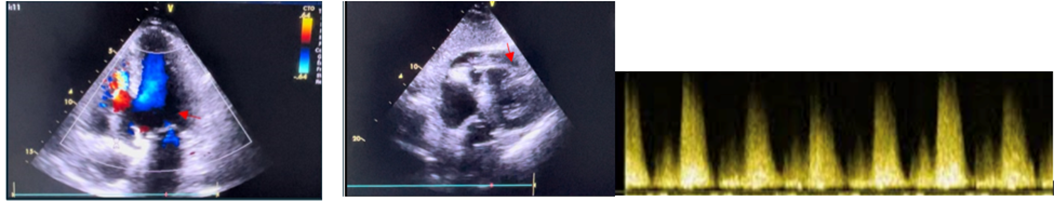

Figure 1: This is a 76-year-old patient admitted with inferobasal STEMI. The echocardiography showed segmental hypokinetic heart disease with preserved systolic function, a ruptured image in the inferobasal segment of the interventricular septum, and a breached right ventricle opposite its free wall, with systolic dysfunction.

Figure 2: This 66-year-old patient was admitted with STEMI anteriorly. Echocardiography showed segmental hypokinetic heart disease with severe LV dysfunction (30-35%), the site of an apical aneurysm, associated with a 7 mm apical muscular IVC image responsible for a left-right shunt.